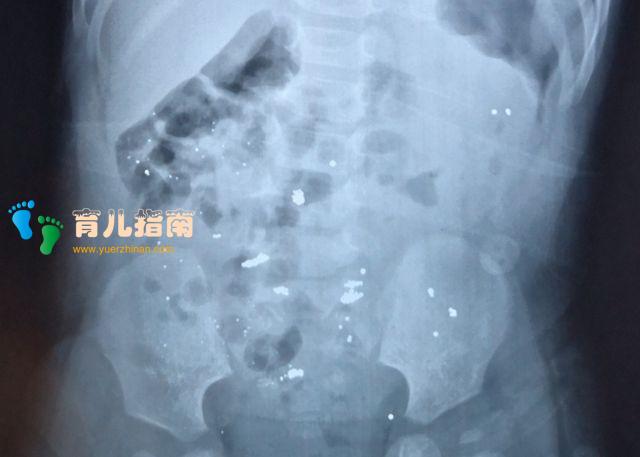

这天年奶奶刚给年年量完体温,想着给他喝点水,谁知道就转身倒水的功夫,回来年奶奶就看到年年从地上捡起破碎的温度计正在往嘴里倒,年奶奶赶紧夺过温度计,然后找来家里的牛奶给孩子喝了,马上送去了医院,医生给孩子处理完说,幸亏了当时的牛奶不然就麻烦了。

孩子如果误食水银怎么办?在发现孩子误食水银后,首先,要让孩子涑口,检查是否有碎玻璃留在口腔内;

然后,手指轻轻的按压几下孩子的咽部进行催吐,尽量让孩子能够吐出刚刚吃掉的东西,可以排出一部分的水银;

再者,送孩子去医院,去医院前或者途中可以给孩子喝一些牛奶来保护孩子的肠粘膜,这样水银被吸收的可能性比较小,但是却可能造成肠胃穿孔,然尽量让孩子不要剧烈运动。